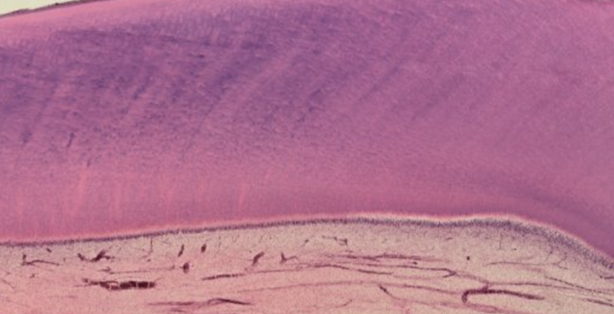

Choose the microphoto, which represents area of the soft palate marked by number 4.